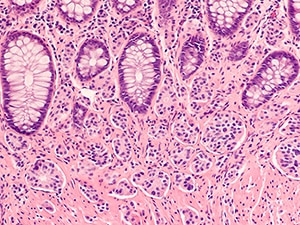

Pediatric patients with certain GEP-NETs, such as the carcinoid colon tumor shown here, can now receive this treatment.

GEP-NETs are neuroendocrine tumors that occur in the gastrointestinal tract or the pancreas. They form from neuroendocrine cells—cells that make hormones, such as those that aid in the process of digestion. Worldwide, around 5.25 out of every 100,000 people are diagnosed with a GEP-NET each year.